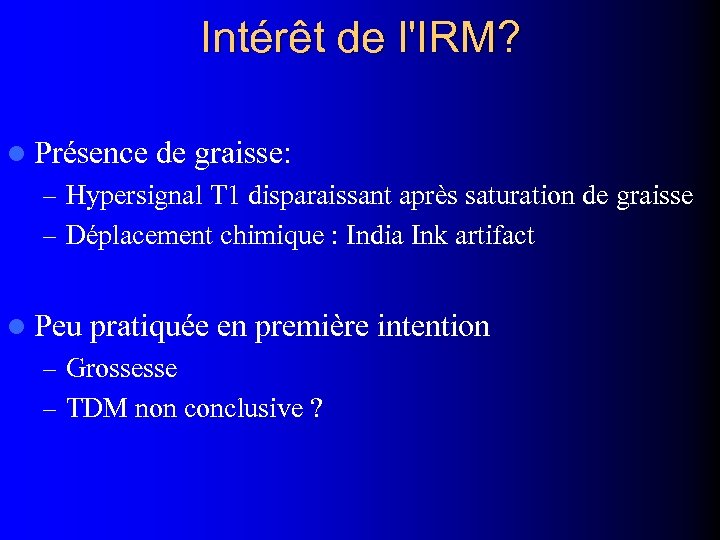

Intérêt de l'IRM? l Présence de graisse: – Hypersignal T 1 disparaissant après saturation de graisse – Déplacement chimique : India Ink artifact l Peu pratiquée en première intention – Grossesse – TDM non conclusive ?

Intérêt de l'IRM? l Présence de graisse: – Hypersignal T 1 disparaissant après saturation de graisse – Déplacement chimique : India Ink artifact l Peu pratiquée en première intention – Grossesse – TDM non conclusive ?